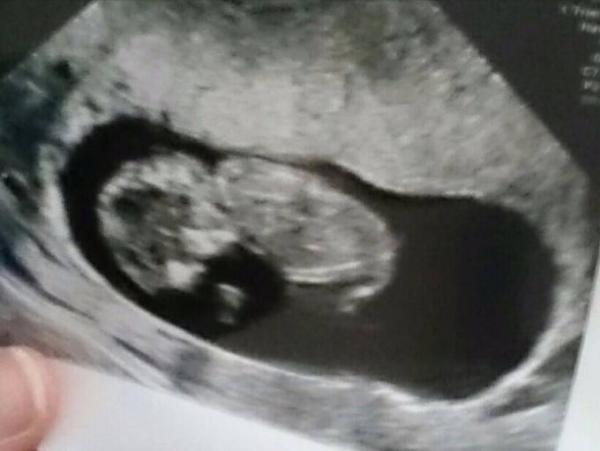

Alles super! Zeitgerecht entwickelt bei 10+6. Also nur ein Tag weiter. Sieht gut aus. Ich bin so erleichtert!!!!

Foto! Und die Größe ist 3,9cm.

Süß!!! Glückwunsch meins ist 3,6 cm. War gestern nämlich im Krankenhaus weil ich dachte das die Niere staut hab das öfter dann hat sie beim us der Nieren noch schnell auf das kleine geschaut